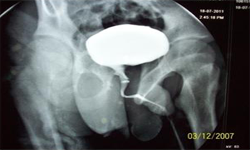

He was evaluated and investigated in detail and planned for artificial urinary sphincter. Preoperatively, micturating cystourethrogram, urodyanmic study, cystoscopy were done. The upper tracts were normal. There was no vesicoureteric reflux, stricture. Bladder capacity was 250 ml, maximum detrussor pressure was 30 cm of water and insignificant residual urine.

Micturating Cystourethrogram Cystometry